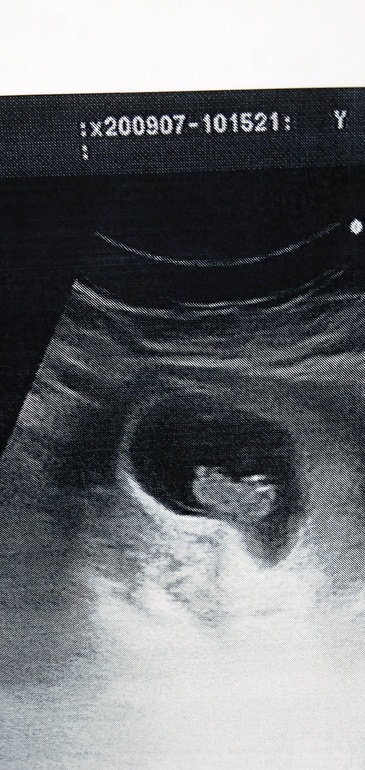

Я сегодня на УЗИ ходила , и увидела и услышала ❤️😍😍😍😍

И фоточку сделали 😍 такая козявочка, почти человечек

вот ❤️

Ой какая кроха)) прелесть. Уже видно где голова , ручки. Прелесть 😍